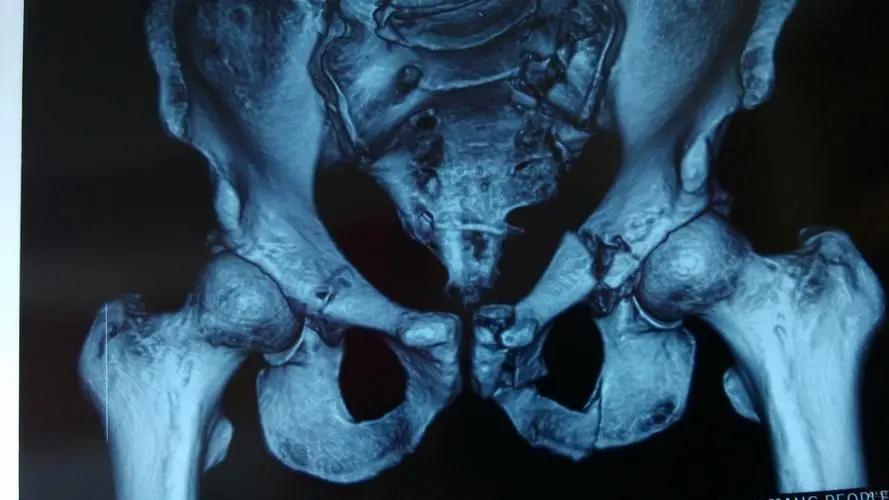

而骨盆后环的稳定性则是由骶骨、两侧骼骨和骶骼关节及周围韧带共同构成的骶髂复合体共同维持,其主要是由双侧髋骨以及骶骨组成。

而骨盆后环主要是指骶髂关节,骶髂关节是人体最重要的关节之一,不仅是组成骨盆后环的重要结构,还在人体重力的传递中起到了重要的作用。

骶髂关节关节面扁平,是由髂骨以及骶骨耳状面组成,彼此对合紧密,关节囊紧张,并且其周围有许多强韧的韧带加强,比如:骶髂前韧带、骶髂后韧带、以及骨间韧带等。

其关节腔狭小的裂隙状, 因而骶髂关节是一种微动关节,这样的结构有利于支持体重和传递重力,在老年人中,骶髂关节部分关节面融合,关节活动基本上消失。

在影像学中,骶髂关节通常被用来评价骨盆损伤稳定性是否遭到破坏,骶髂关节是否有移位是其判断标准。